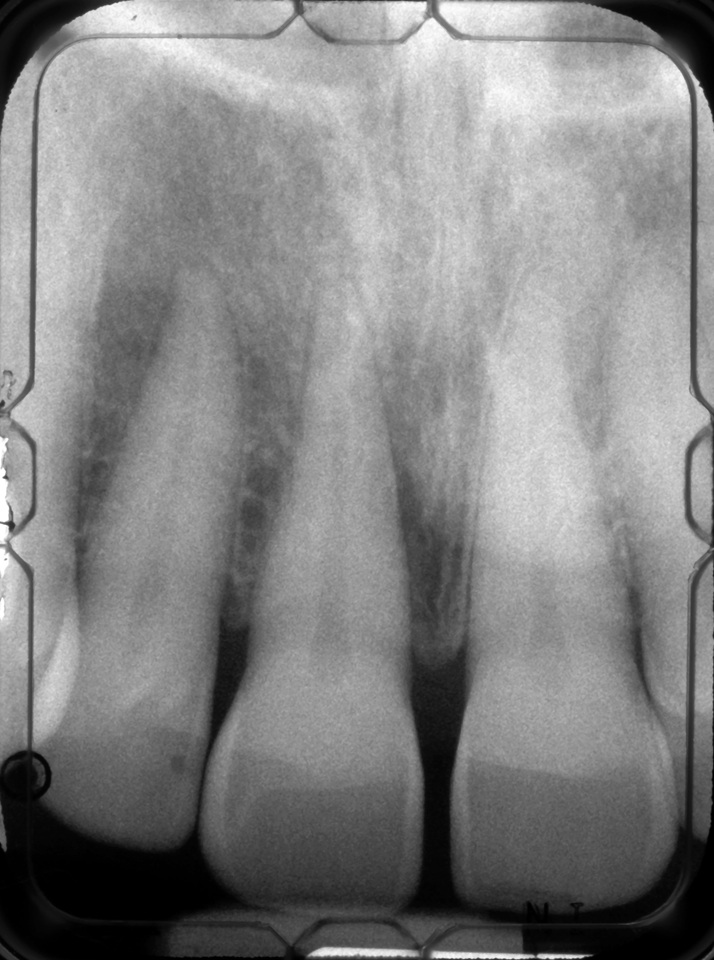

Facial bone loss and a mesial vertical defect.

Fig. 3

Then, too, are opportunities to prepare the site for regeneration by coupling therapies, applying an enamel matrix derivative, along with traditional bone grafts of demineralized freeze-dried bone allograft; potentially, gains in attachment with minimal probing depth and retained papilla may avoid the need for an implant (Figure 2 through Figure 7).